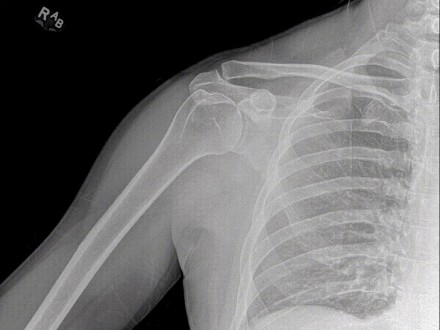

This new technology is dynamic digital radiography, also known as DDR, and it allows physicians to watch a patient’s motion of lungs and diaphragm during breathing to better analyze and diagnose suspected lung nodules, chronic obstructive pulmonary disease, known as COPD, and interstitial lung disease and to determine whether the diaphragm is paralyzed. Doctors can also observe the full range of joint motion to help evaluate suspected injuries.